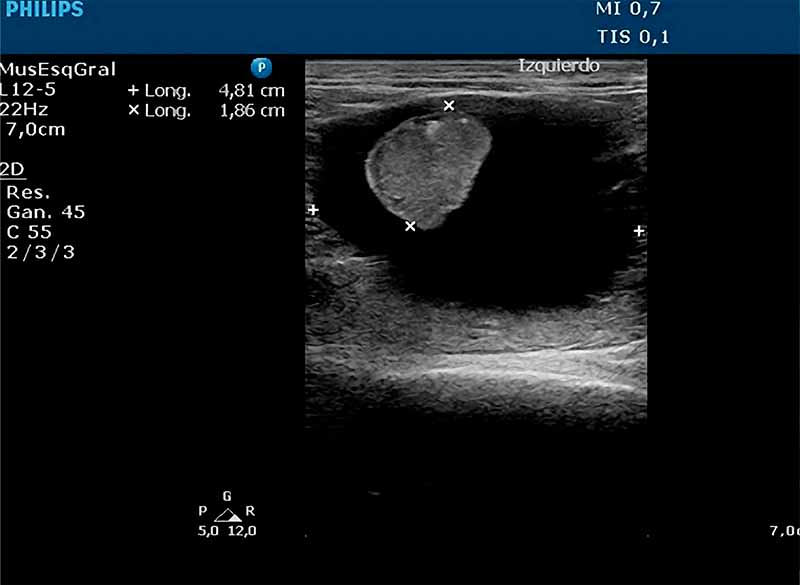

Hallazgos Ecográficos:

Se evidenció atrofia renal asociada a efusión perirrenal en uno de los órganos, mientras que el riñón contralateral presentó morfología y ecogenicidad conservadas.

Se realizó nefrectomía del riñón afectado. Tras 72 horas de hospitalización con soporte fluidoterápico, el paciente experimentó una evolución postoperatoria favorable con recuperación clínica satisfactoria.